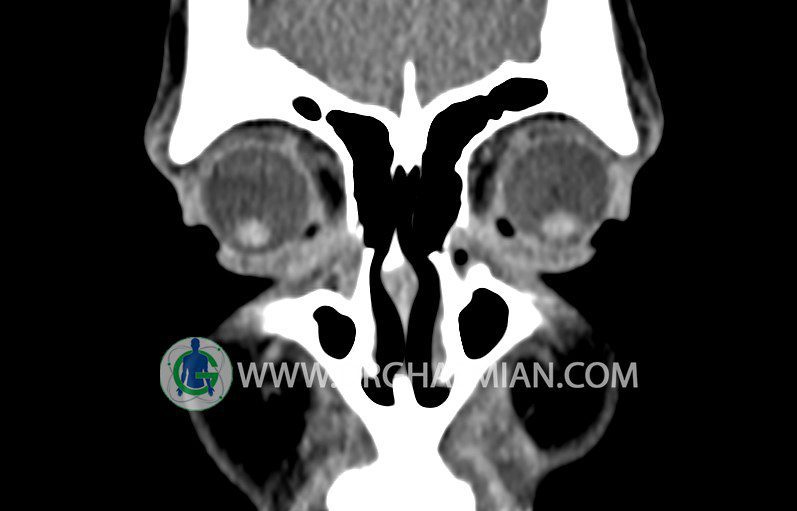

سی تی اسکن سینوس ها یک روش تصویربرداری است که با استفاده از تشعات ایکس تصاویری با جزییات از ناحیه خالی داخل صورت (سینوس ها) ایجاد میکند. در این کیس استئوم فرعی سینوس در دیواره سینوس ماگزیلاری، انحراف سپتوم و کونکا بولوزا مشاهده می شود.

در HRCT اسپيرال از سينوس هاي پارانازال مقاطع کرونال و آگزيال ( 16 اسلايس و مقاطع ظريف 1.5 mm بدون فاصله ، با پنجره استخواني و نسج نرم ) :

ضايعه ای در سينوسهای فرونتال، اسفنوئيد، ماگزيلاری و اتموئيد مشهود نيست.

شواهدی از توده، سطح گاز – مايع، کدورت سينوسها، افزايش ضخامت مخاط ديواره سينوسها، اروژن ديواره سينوسها و دنسيتی غير طبيعی ديده نمی شود.